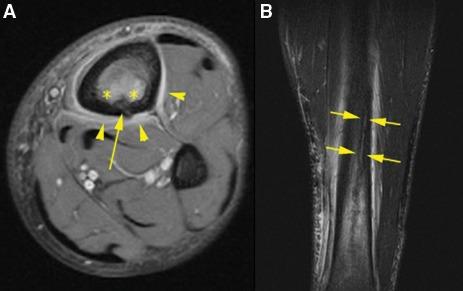

Orthopaedic magnetic resonance imaging challenge.

Bodor Daniel, Awh Mark H, Stadnick Michael E

Sports Health. 2010 Jul;2(4):351-5. doi: 10.1177/1941738110373452.